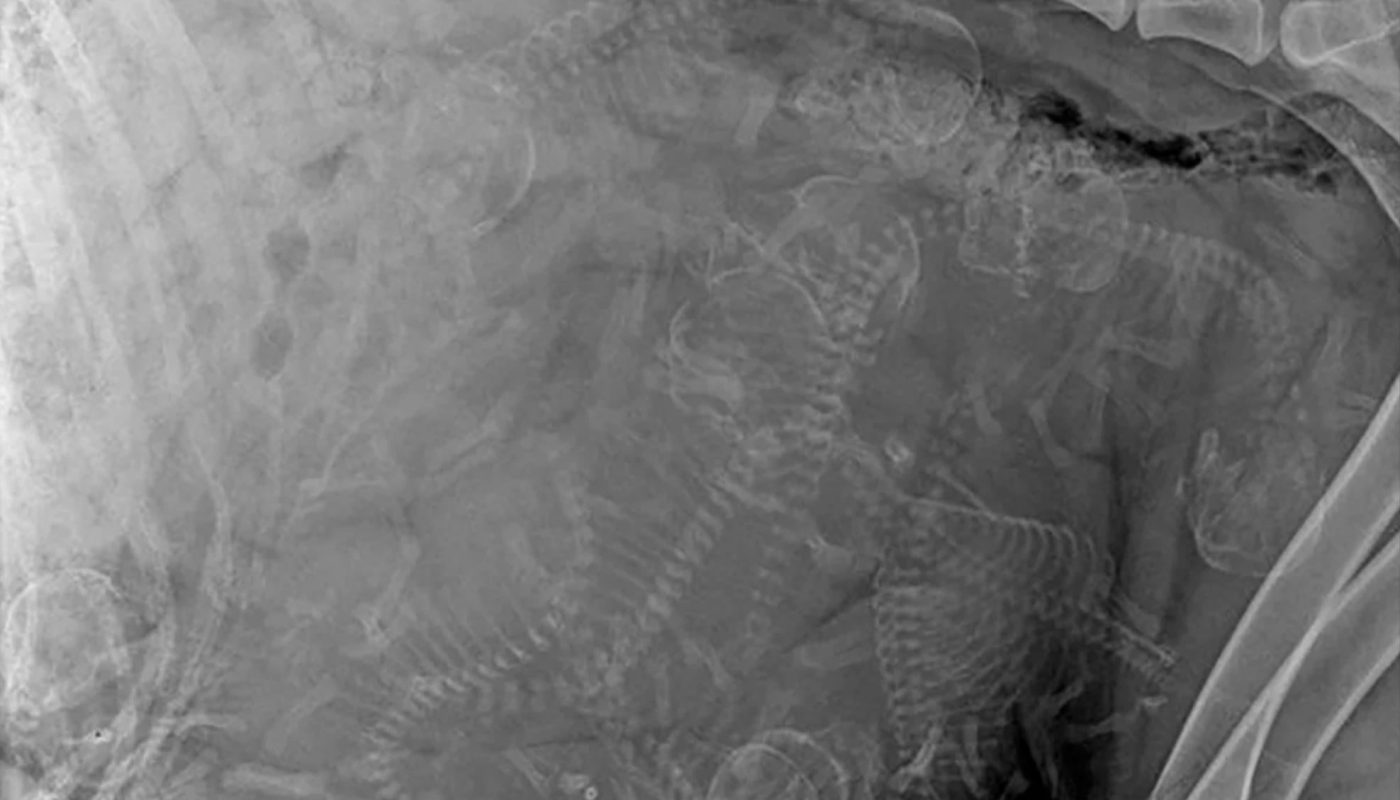

X-Ray of pregnant dog. Not sure how many puppies?

- Overlapping puppies: Skeletons can overlap, making it hard to distinguish individuals.

- Fetal movement: Active pups may shift during imaging.

- Breed size: Small litters in large breeds (e.g., Great Danes) are easier to count than large litters in small breeds (e.g., Dachshunds).

Tip: Vets often take multiple angles (e.g., side and belly views) to improve accuracy. Expect a margin of error of ±1–2 puppies.